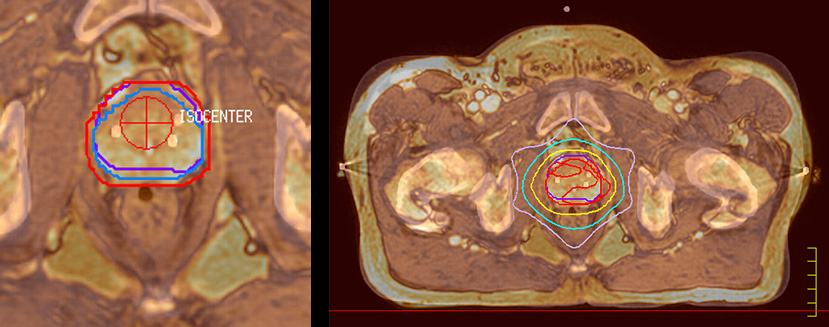

“The biggest problem for CT-based planning, especially in prostate, is you can’t see the cancer very well,” says Dr. Stevens. “On CT it can be quite challenging to see the edge of the prostate especially at the apex. When the edge of the prostate can’t be delineated well on CT, radiation oncologists will increase their margins a little bit so they don’t miss it, but that can also increase toxicity.” “Using MR, the prostate is well delineated. We quickly see the edges of cancerous tumors like in prostate cancer, and as normal structures can be defined, we can optimize the treatment plan to protect these organs and their normal function. This can potentially improve the outcome. And it improves workflow as well. We can contour more quickly, confident that the tumor is going to be in the field.” “The Ingenia 3.0T MR scanner provides high resolution allowing us to make scans fast for the patients. It also gives the potential to include methods like MR spectroscopy and diffusion weighted Imaging, which we’re in the process of doing right now,” Dr. Stevens adds.

“When a patient registers, first CT simulation and MR simulation are done, followed by CT-MR registration on Pinnacle3. Then the target and normal organ delineation is performed on MR images. Meanwhile we create a reference CT image for online treatment and localization correction. During the treatment phase we can perform additional MRI scans to visualize the anatomy changes and create an adaptive plan. This plan basically adapts the treatment plan to the changes.” “Along with its great benefits, MR has introduced some new challenges,” Dr. Stevens says. “Radiation therapy teams generally have no experience with MR. The Philips training helped us to implement fully the things we can do with the Ingenia MR-RT system. So the training, as well as having a good MR physicist, is critical.”